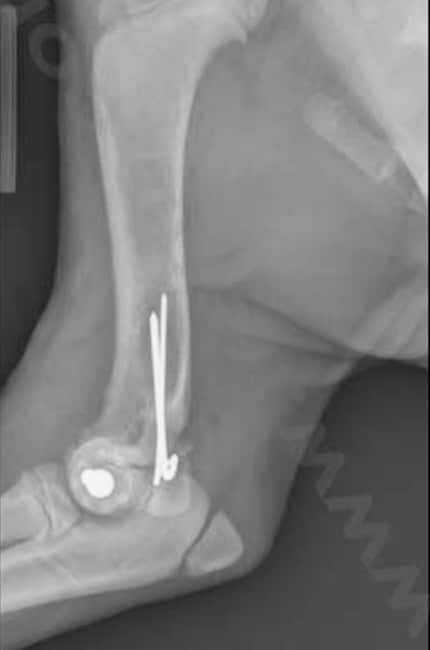

Le traitement est, comme pour beaucoup de fractures chez le chien, chirurgical. Il faut alors réduire la fracture pour réaligner les abouts osseux et maintenir l’os dans sa conformation naturelle puis la stabiliser avec des implants, le plus souvent des broches qui limitent moins la croissance.

La fracture est réduite, le plus souvent avec des broches et parfois des vis. La quantité de matériel orthopédique est limitée afin de traumatiser le moins possible l’os en croissance. Des radiographies sont réalisées après l’intervention.

Votre chien doit être réexaminé 3 semaines et 6 semaines environ après la chirurgie afin de s’assurer que tout se déroule correctement. Des radiographies sont souvent faites pour suivre la croissance osseuse et s’assurer qu’aucune complication en rapport avec la croissance osseuse n’a lieu.

Le retrait du matériel orthopédique (broches et vis) est parfois recommandé après consolidation osseuse.